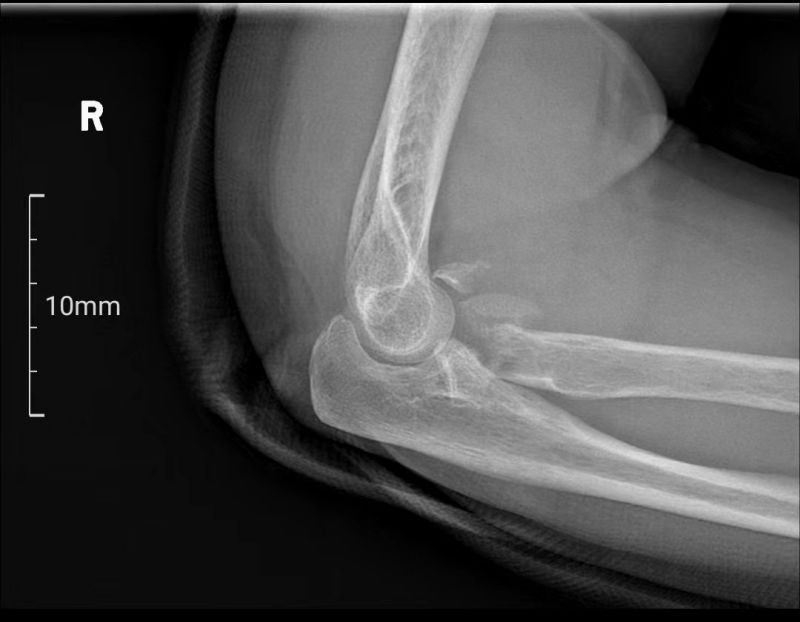

患者梁女士因不慎跌倒导致右肘关节疼痛并活动受限,经X线检查确诊为肘关节恐怖三联征。面对这一复杂病情,张立主任迅速组织科室医生及3D打印中心技术人员进行病例讨论,并决定采用3D打印桡骨小头置换术进行治疗。

肘关节恐怖三联征,作为一种复杂的肘关节骨折脱位类型,同时涉及肘关节后脱位、桡骨头骨折及尺骨冠突骨折三种损伤,其治疗难度极高。面对这一挑战,南溪山医院创伤骨科与手外科张立主任团队凭借其丰富的临床经验和前瞻性的技术视野,决定采用先进的3D打印技术为患者提供个性化治疗方案。